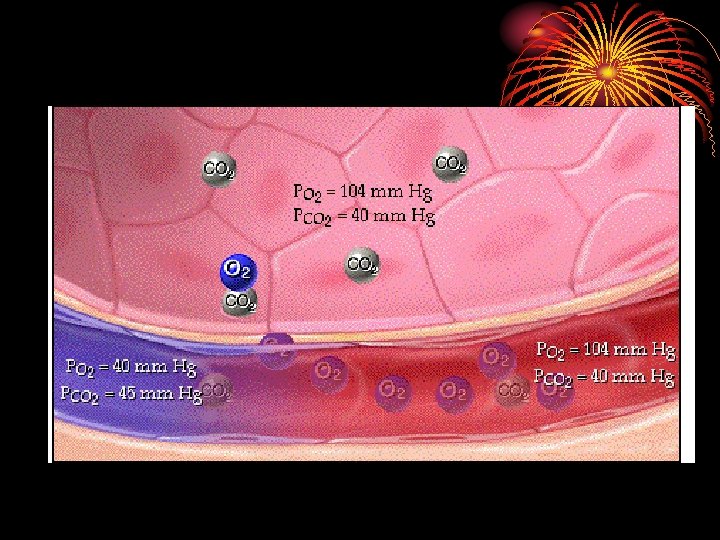

Gas transport between lungs and tissues: • Oxygen diffuses out of alveolar gas into the blood stream and CO 2 diffuses from the blood into the alveoli down their partial press. gradients. • Diffusion capacity of the lungs for a given gas is directly proportional to the alveolocapillary membrane (pulm. epithelium, capillary endothelium & their basement membranes) and inversely proportional to its thickness.